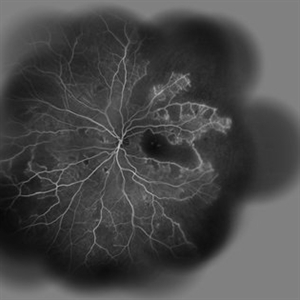

Behcet's Disease Behcet's DiseaseMar 13 2013 by Hamid Ahmadieh, MD Wide field FA of the left eye of a 23-year-old man with retinal vasculitis due to Behcet's disease . Photographer: Solmaz Shahmohammadi , Negah Eye Center, Tehran Imaging device: Heidelberg Spectralis Condition/keywords: retinal vasculitis